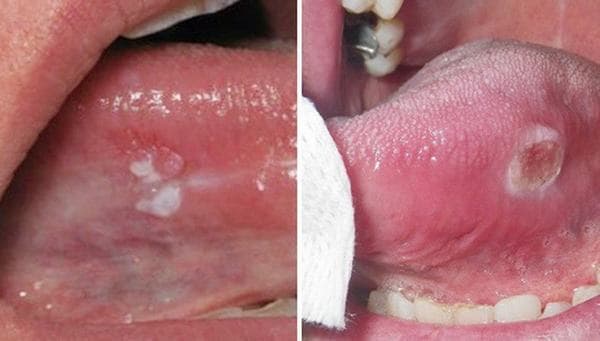

Hình ảnh ung thư lưỡi giai đoạn đầu thường chỉ là những vết loét hay nhiệt trên lưỡi nên nhiều người bỏ qua, cứ nghĩ vài ngày sẽ khỏi.

Với ung thư lưỡi, các vết loét hay nhiệt miệng này sẽ kéo dài trong thời gian dài, không khỏi. Vết loét lớn dần và có thể lan ra ngoài lưỡi đến môi hoặc vòm họng, gây đau đớn khó chịu. Khi quan sát kỹ sẽ thấy có mủ hoặc chảy máu ở vết loét.